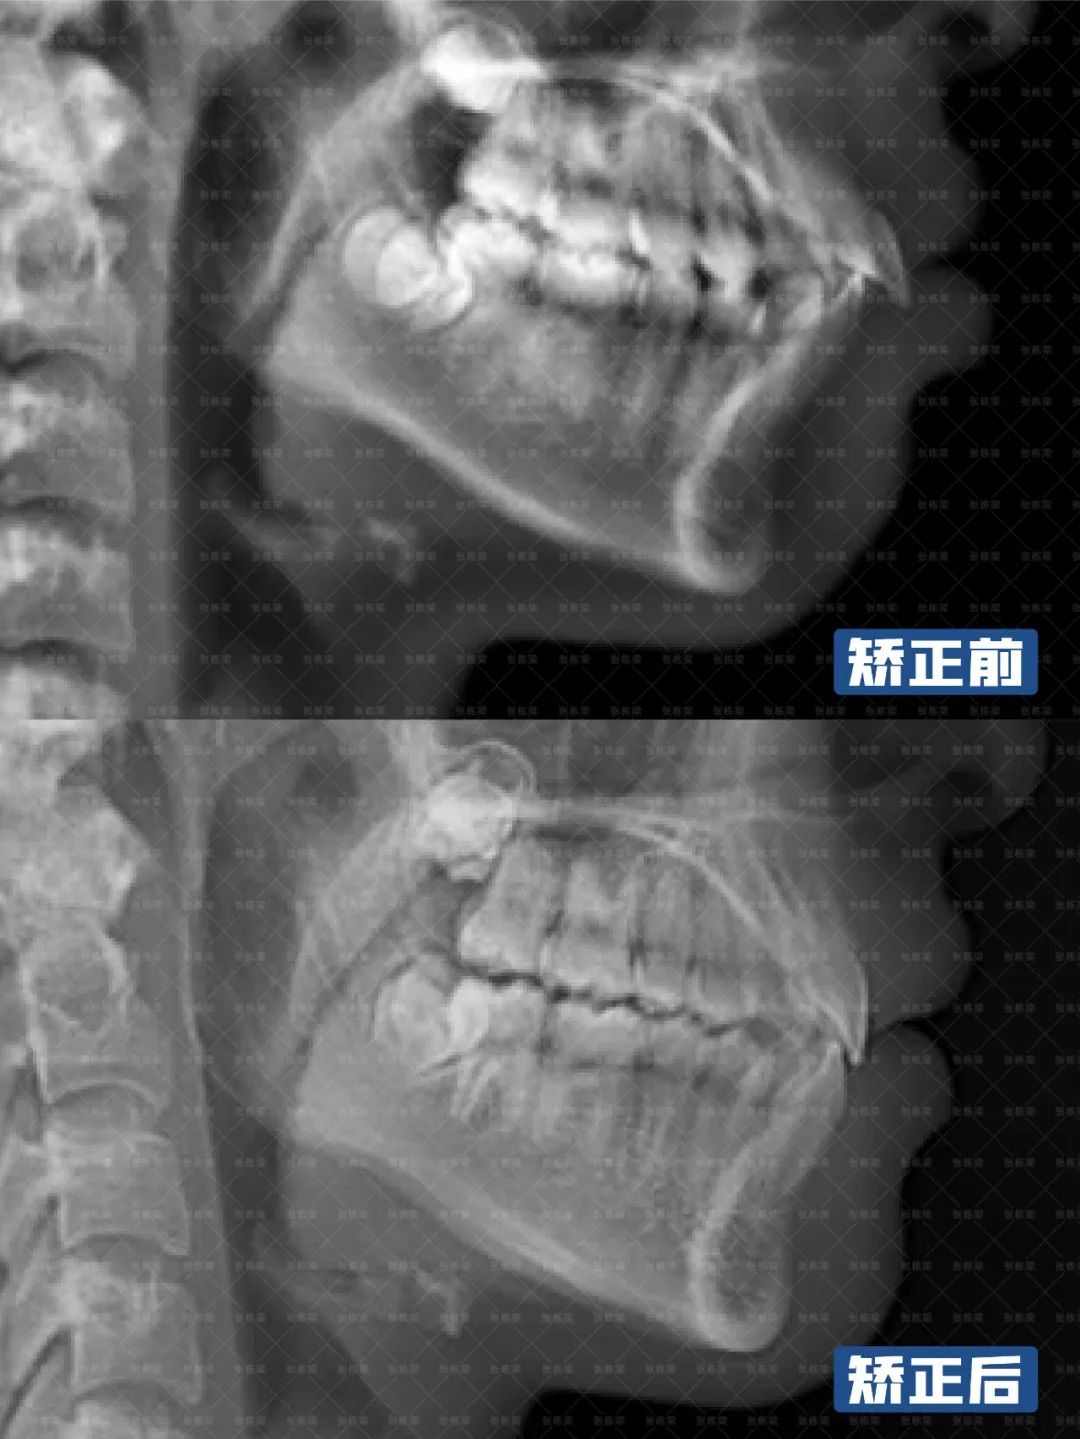

通过牙片资料检查孩子有骨性II类倾向,重度深覆合深覆盖,牙齿存在散在间隙。第一阶段佩戴隐形牙套,隐形矫正结束后,上颌内收,颏部前伸,侧貌形态改善良好,前牙达到正常覆合覆盖。

后续开展第二阶段时,将采用Grace定制化硅胶牙套,精细调整匹配上下颌弓形,整平颌平面,利用孩子生长发育潜力,继续引导下颌向前。

考虑到孩子还在生长发育阶段,还有一定的生长潜力,综合考虑孩子的牙齿、面型情况之后,制定不拔牙矫正方案,使用隐形牙套。

关键一点是通过推磨牙向远中+扩弓来获得间隙,解决前后牙距离大、内收排齐牙齿、把上下牙角度调直,调整咬合平面角度,创造下巴前伸的条件。